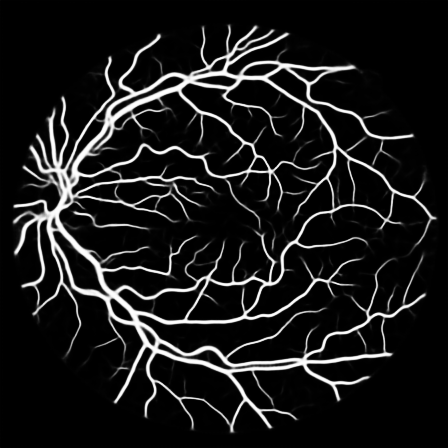

To justify the performance of our model, we compare the 4 metrics with 8 representative previous works from all 3 open-access datasets. The comparison results presented in Table 1 show that our MP-Net model outperforms the state-of-the-art methods regarding accuracy and in all three datasets, which meter the practical prediction quality and the overall prediction quality independent on thresholding specifications. The advancement is greater in the DRIVE dataset. It’s related to the fact that the DRIVE dataset contains more thin vessels, which is the main target of our model. Specificity is also the highest in DRIVE and CHASE_DB1 while sensitivity is highest in STARE. Particularly, our method outperforms ML-UNet [2] and JL-UNet [4] which adopt a different multi-class approach to also especially tackle the thin-vessels challenge. Figure 2 shows an example of our segmentation maps on DRIVE. As can be seen, most thin vessels and boundary areas have been meticulously picked up.